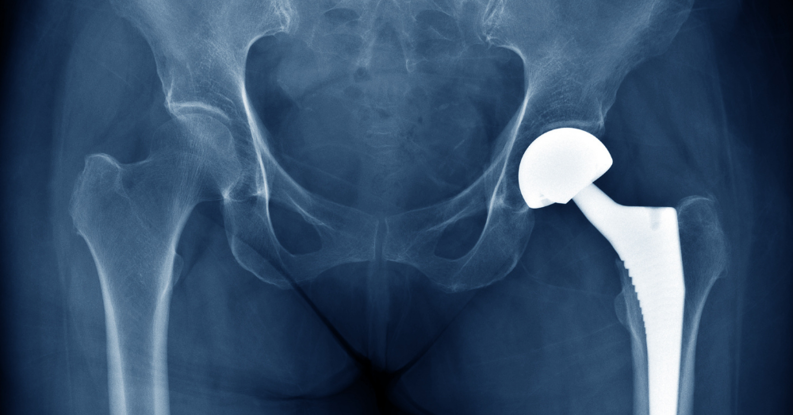

Joint Surgery

Joint replacement surgery can make a big improvement in your quality of life. Our program provides an environment that emphasizes wellness in joint replacement procedures and maximizes patient recovery efforts through education, a culture of early mobility, family involvement and group interaction. We utilize evidence-based practices to get you on the path to a healthy, pain-free, active lifestyle quickly, with transition to home 1-2 days after surgery and return to normal activities within 6-12 weeks.